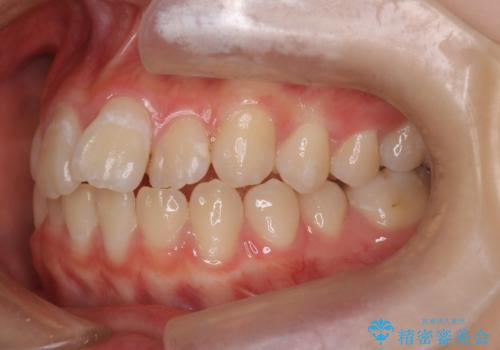

- 前歯のガタツキが気になるとのことで来院されました。

前歯のガタツキに加え、奥歯の噛み合わせにも問題があったため、マウスピース矯正で治療し改善しました。